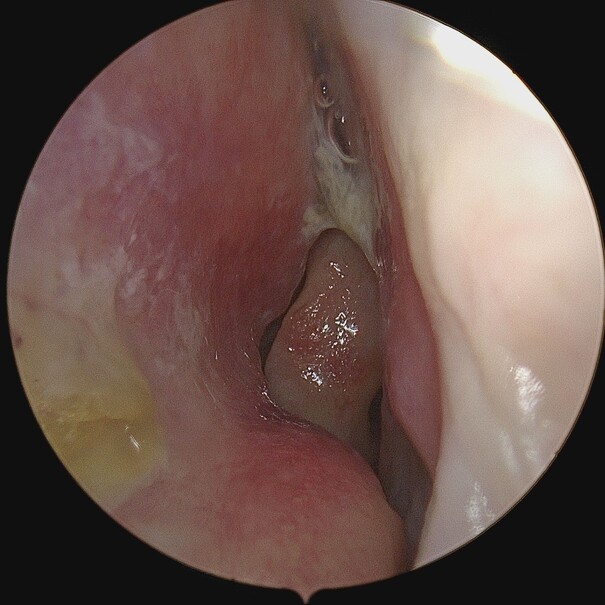

Enlarged Nasal Turbinates (Turbinate Hypertrophy)

Turbinate enlargement refers to the condition where the nasal turbinates become swollen or enlarged. This enlargement can obstruct airflow through the nose, leading to symptoms such as nasal congestion, difficulty breathing and sometimes even snoring . They can also secrete large amounts of mucus.

Some of the causes of turbinate enlargement are allergic rhinitis (hay fever , vasomotor (non-allergic) rhinitis, chronic sinusitis, nasal polyps , abnormal growth of the central turbinate, deviated nasal septum or environmental factors like dry air, irritants, pollutants, or changes in temperature. Turbinate enlargement can also be congenital with very large turbinates running in the family.

This condition can be diagnosed with a thorough examination of the nose to assess for nasal obstruction and signs of inflammation. A nasal endoscopy may be required combined with CT scans to assess the severity of any structural abnormalities or chronic sinusitis. In some cases, turbinate enlargement can be medically managed by use of steroid sprays, antihistamines, decongestants or saline nasal irrigation, along with some lifestyle changes like using a humidifier and minimising exposure to allergens. Otherwise, surgical options may have to be considered. Various techniques effectively reduce their size, like turbinoplasty that has evolved into minimally invasive procedures like Minimally Invasive Powered Endoscopic Turbinate Reduction (MIPET), or use of coblation; septoplasty or sinus surgery (FESS), whereby sinus drainage and ventilation are improved especially in cases where chronic sinusitis is the cause.